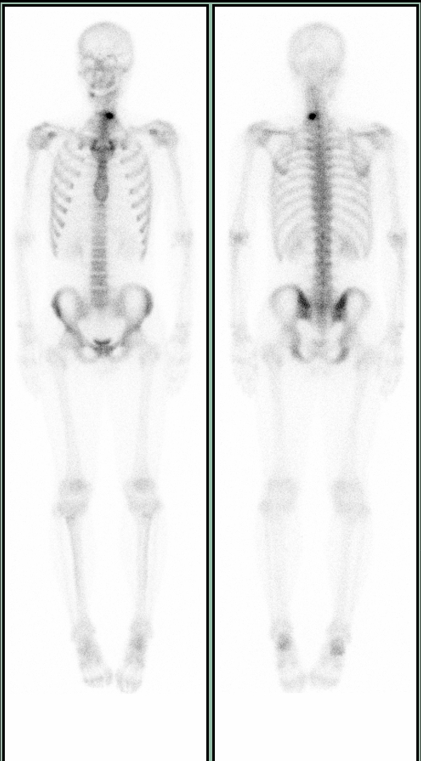

當懷疑或已知患有骨骼疾病,例如腫瘤、風濕性疾病、感染、外傷、代謝性骨病等,可能需要進行骨顯像(也叫做骨掃描)。檢查簡介:骨顯像,顧名思義,是使骨骼顯影的一種檢查,可以顯示全身或局部,可以進行平面或者斷層顯像。檢查科室:核醫(yī)學科。檢查流程:檢查前:掛號(核醫(yī)學科或其他首診科室)→開具骨顯像申請單→預約(門診樓地下二層核醫(yī)學科)檢查當日:分診→注射99mTc-MDP→等候3小時以上→排尿→進行掃描→離開取結(jié)果:下一個工作日注意事項:孕婦和哺乳期女性進行骨顯像需慎重。哺乳期女性如果進行骨顯像,需要停止哺乳4小時以上。骨掃描無需空腹,正常飲食即可。骨掃描均需要靜脈注射顯像劑,充分按壓,避免滲血。注射顯像劑后,根據(jù)自身情況盡量多飲水。注射顯像劑后,排尿需擦拭干凈尿道口,避免尿液沾污衣褲,如果不慎沾污衣褲,請及時更換,或告知我科室技術(shù)人員。注射顯像劑后,需要等待3小時以上進行掃描。一般來說全身平面掃描時間約為15分鐘左右,如果加做局部或者斷層顯像,另外需要5-15分鐘左右,請合理安排時間,耐心等待。掃描之前,需要去除金屬物品(項鏈、手鐲、鑰匙、手機、皮帶扣等)。掃描過程中,保持固定姿勢,不要移動身體。檢查當日請攜帶外院檢查、化驗、病歷等資料,備用。